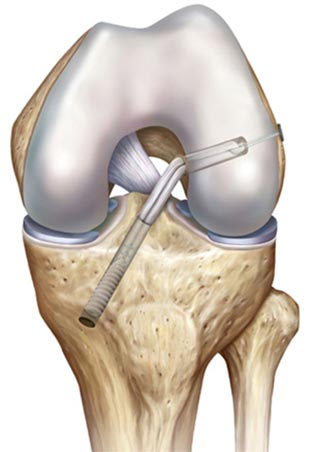

Vor dem Einbringen des Transplantats müssen noch störende Fasern des alten Kreuzbandes beseitigt und störende Knochenvorsprünge entfernt werden. Für das neue Kreuzband wird in der Folge über den Schnitt an der Schienbeinvorderkante eine Bohrung angebracht, in der das Implantat verankert werden kann. Als nächster Schritt wird daraufhin die Bohrung im Bereich des Oberschenkelknochens durchgeführt. Am Wichtigsten beim Setzen der Bohrkanäle ist eine exakte Positionierung der Bohrungen, so dass das neue Kreuzband möglichst genau den Verlauf des Originalkreuzbandes nimmt. Hierfür finden spezielle Ziel- und Messgeräte Anwendung.

EINBRINGUNG UND FIXIERUNG DES TRANSPLANTATS

Das in mehrere Schlaufen gelegte Transplantat wird auf der einen Seite mit einem sogenannten Button befestigt, einem kleinen Titanstift der für die Verankerung außerhalb des Oberschenkelknochens benötigt wird. Sind Transplantat und Kniegelenk entsprechend präpariert, wird das Transplantat über die vormalige Sehnenentnahmestelle am Unterschenkel in das Gelenk eingebracht und über den Bohrkanal im Oberschenkelknochen herausgezogen. An der äußeren Knochenkante verhakt sich sozusagen der Titanstift, so dass das Transplantat nicht mehr nach unten entweichen kann.